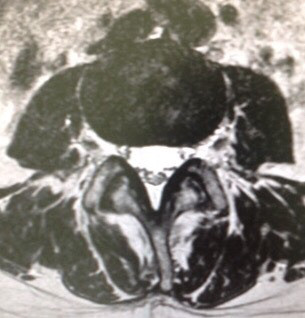

図の左側なんて狭苦しいでしょう‼️コレが脊柱管の『狭窄』と呼ばれる状態ですね。実際のMRIをどうぞ。まずは正常な部位。

次が狭窄部位。一目瞭然でしょうが・・・では、この方にどんな症状が❓

次が狭窄部位。一目瞭然でしょうが・・・では、この方にどんな症状が❓痛み、しびれ、間歇性跛行、膀胱直腸障害・・・など、

ナニモありません‼️